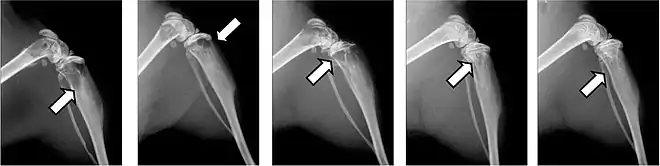

- Vues de fractures pathologiques

Fracture pathologique de l'humérus sur une métastase de carcinome du rein

Fracture pathologique du bras gauche sur une métastase osseuse de cancer du sein

Les fractures pathologiques sont des fractures de l’os qui surviennent sans atteinte extérieure, à cause d'un affaiblissement pathologique de la matrice osseuse. Les métastases surtout ostéolytiques, mais aussi parfois ostéocondensantes, affaiblissent l’os concerné qui selon les circonstances peut être sursollicité par des contraintes mécaniques faibles, et rompt. Ces fractures peuvent survenir dans des situations de tous les jours, comme le fait de se lever d'un siège ou de déplacer le patient[77]. Pour les métastases ostéocondensantes, l'épaisseur de l’os est certes augmentée, mais sa solidité est abaissée par sa construction complètement non structurée[6]. Dans le domaine de la colonne vertébrale, elles peuvent conduire à des enraidissements[65].

Ce sont la plupart du temps les côtes ou les corps vertébraux qui sont atteints par les fractures. Les fractures dans les os longs, en particulier au col du fémur, présentent une gravité particulièrement élevée et sont le principal motif pour une intervention chirurgicale. Les fractures des corps vertébraux peuvent conduire à des syndromes de compression médullaire[65].